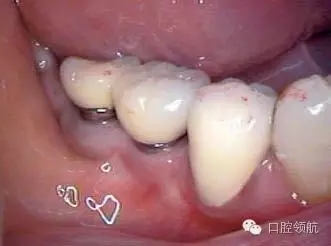

患者, 5 3 歲, 女, 2 0 0 2 年2 月(右下第6、7顆牙) 接受種植治療,采用了一次手術(shù)的方法,SwissPlus種植體(Zimmer公司,直徑3.7mm×長徑10.00mm),6個月后取印模,制作混合陶瓷上部修復(fù)體(圖1)。

圖1 上部修復(fù)體安裝后的口內(nèi)照片